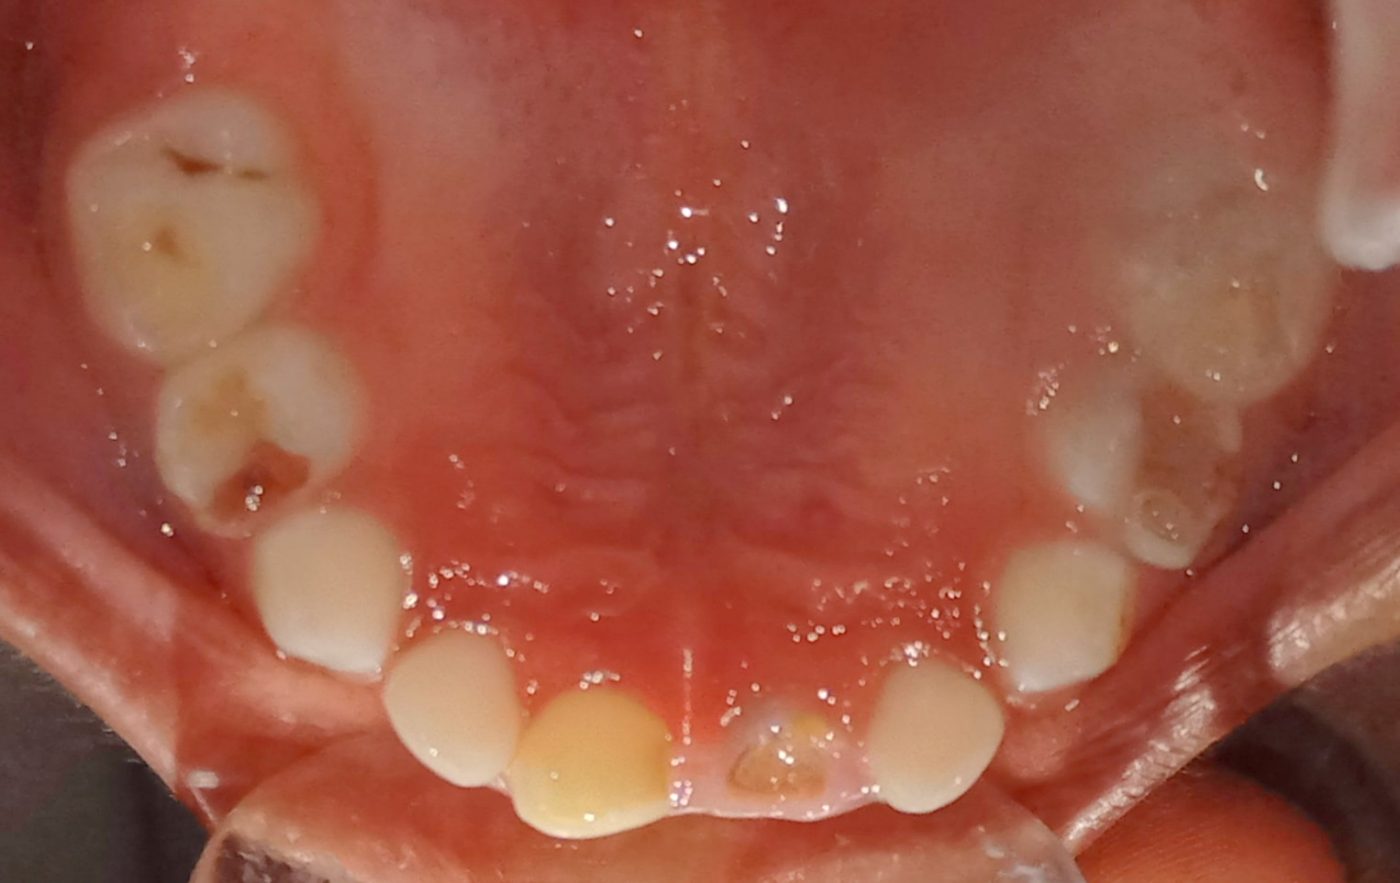

We at the Department of Pediatric & Preventive Dentistry focus on comprehensive oral health care needs of a child from infancy to adulthood and provide comprehensive, therapeutic as well as preventive care to all children including those with special care needs.